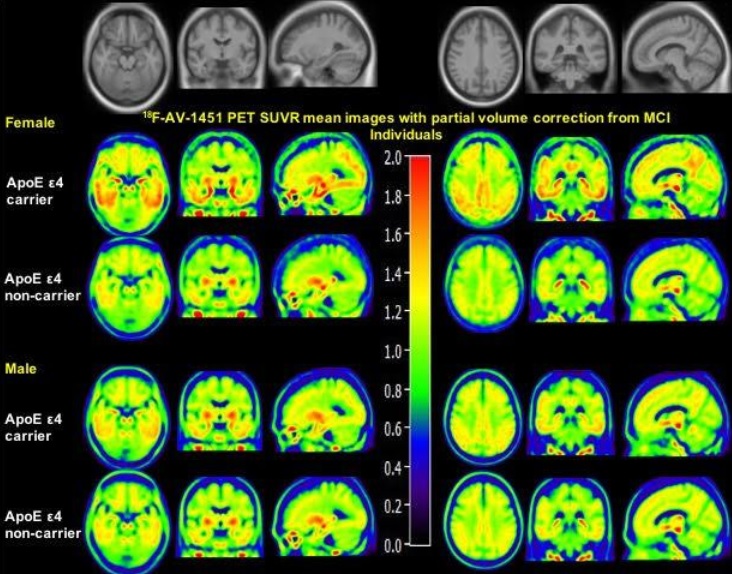

Le sexe affecte l'accumulation de protéine tau dans le cerveau, révèle cette étude par imagerie moléculaire, présentée lors du Congrès 2019 de la Society of Nuclear Medicine and Molecular Imaging. La TEP (tomographie par émission de positons (TEP) ou pet scan) montre que les femmes porteuses de l'allèle ApoE 4 sont plus vulnérables que les hommes à cette accumulation de tau dans le cerveau.

Cette étude transversale menée auprès de 131 sujets âgés en moyenne de 77 ans, dont 66 femmes à cognition « normale » et 97 sujets atteints de déficience cognitive légère dont 39 femmes a évalué les dépôts de tau en prenant en compte les facteurs de confusion possibles (âge et niveau d’études notamment). L’analyse montre que :

- les femmes avec mutation ApoE ε4 sont plus vulnérables que les hommes à l’accumulation de tau,

- le sexe ne module pas en revanche le dépôt de tau associé à ApoE ε4 dans le cerveau des participants en bonne santé cognitive ;

- mais le sexe module l'effet de l'ApoE ε4 sur le dépôt de tau dans le cerveau des participants au stade précoce de la maladie d'Alzheimer ;

- ce constat vaut pour le cortex entorhinal, l’amygdale, le gyrus para-hippocampal et le cortex cingulaire postérieur. De manière frappante, les femmes en déficience cognitive connaissent une augmentation plus importante du dépôt de tau associé à l’ApoE ε4 dans toutes ces zones, vs leurs homologues masculins (voir visuel).